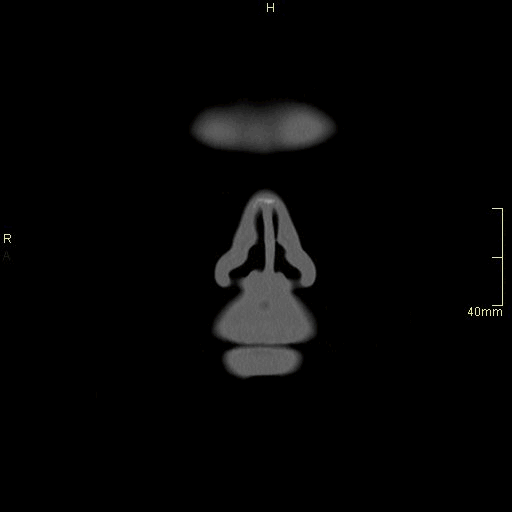

CT Facial Bones/Sinuses Contrast- Bone window (coronal)